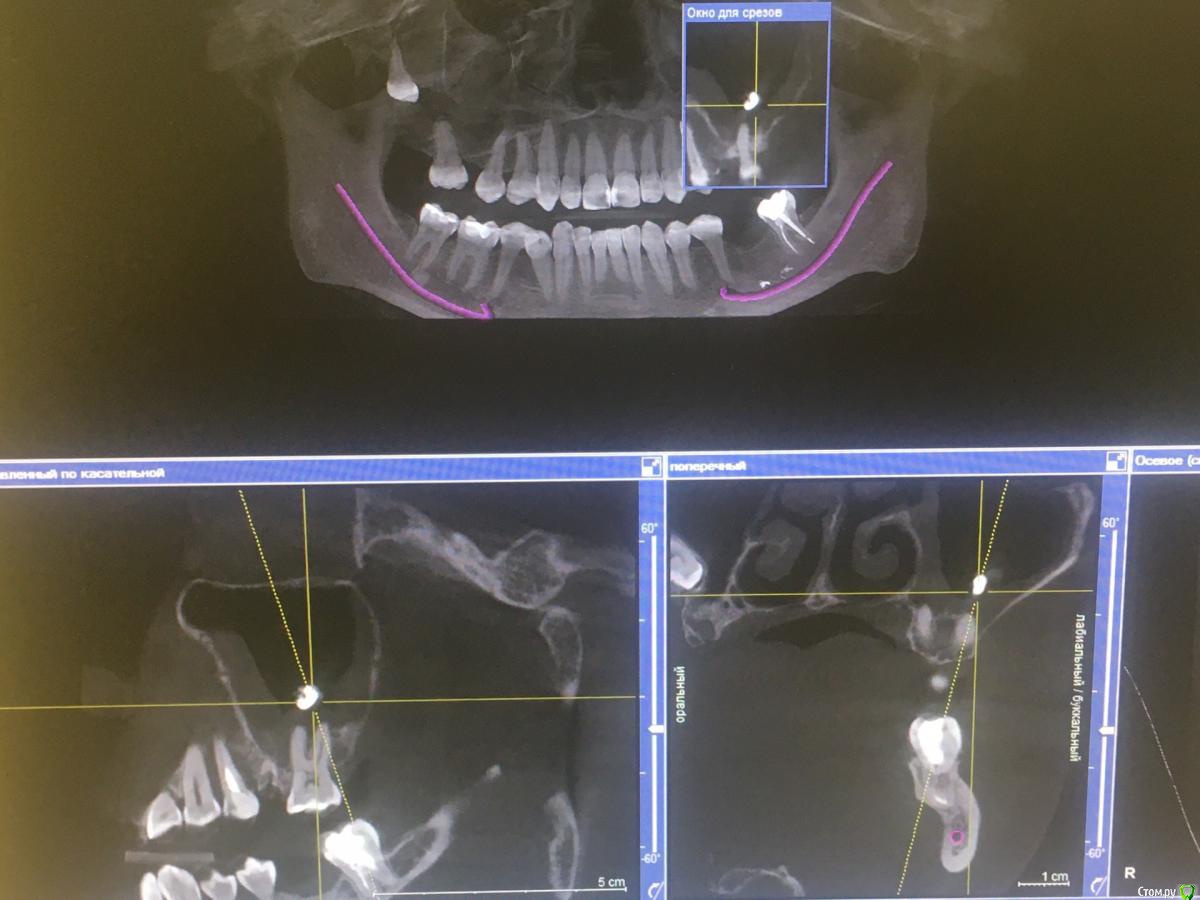

967 Опубликовано 27 февраля, 2020 Поделиться Опубликовано 27 февраля, 2020 Уважаемые коллеги обратилась пациентка, 3 года назад было эндо 25 зуба с выводом материала в пазуху, через год с ее слов начался синусит, проходила лечение у лора, нюансы лечения не знаю, но в итоге лор направил к стоматологу на удаление причинного зуба, далее вопрос от пациентки можно ли удалить из пазухи инородные тела сразу с удалением зуба, я ответил что могу только удалить зуб, в пазухе работать не буду, каким способом устранить проблемы в пазухе? удалить зуб и направить после к лору на эндоскопию, или же вообще не браться за удаление, отправить в члх для удаления вместе с ревизией пазухи? пациентка уже обходила несколько клиник не получив толком ответа, хотелось бы выбрать верную тактику, на данный момент радикс 25 зуба без симптоматики, кт пациентка принесла свое, такую программу я первый раз увидел, поэтому за качество снимков пока извиняюсь, направлю на другое кт по необходимости Ссылка на комментарий

967 Опубликовано 28 февраля, 2020 Автор Поделиться Опубликовано 28 февраля, 2020 Я правильно понял что там корень остался? Достаньте сперва его. Потом к лор-ам по показаниям.это не корень, это силер, просто по снимку так кажется, в обл 25 силер не далеко от апекса, над 26 зубом инородное тело, не похожее на силер, хотя возможно и он мигрировал, но это все надо оттуда удалить желательно малоинвазивно, из ответов выше я склоняюсь все таки к лору, так что спасибо коллеги за ваши ответы Ссылка на комментарий